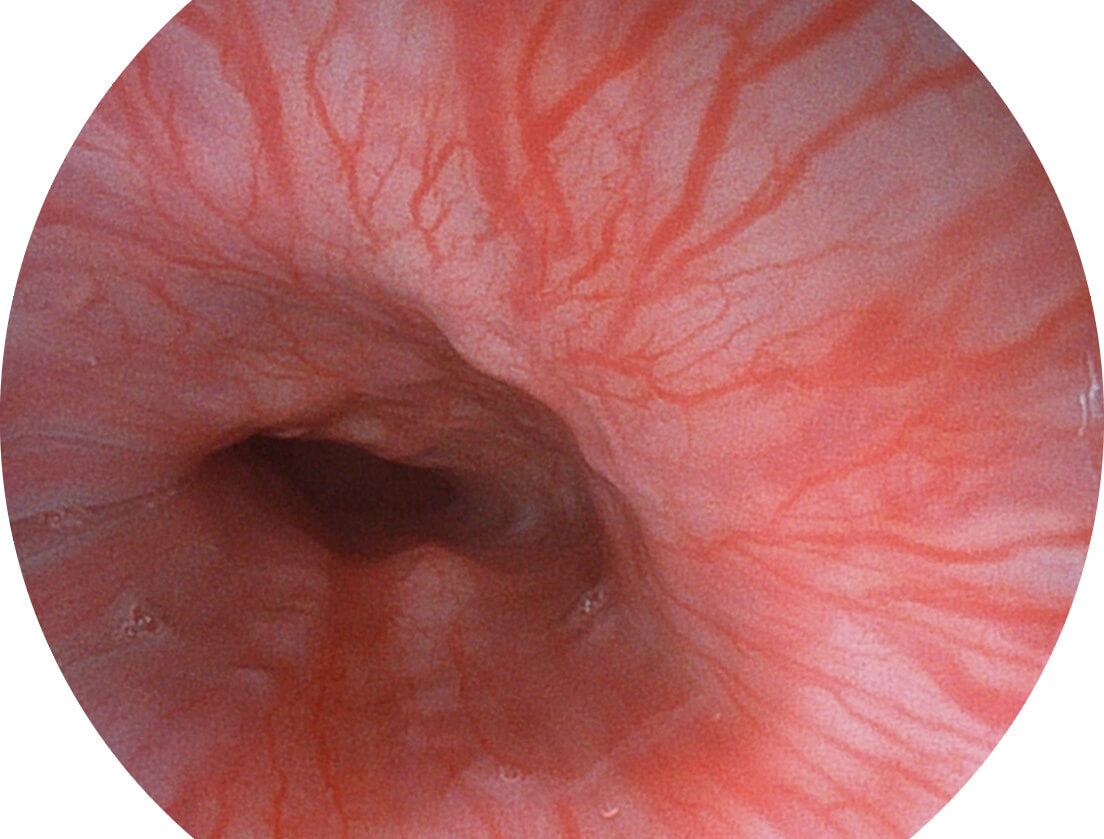

图像具有高亮度、高黏膜血管颜色对比度的特点,且不改变粘液、食物残渣、粪便的基本颜色,可在中远景下进行观察,助力消化道早期疾病的诊断。

SFI图像